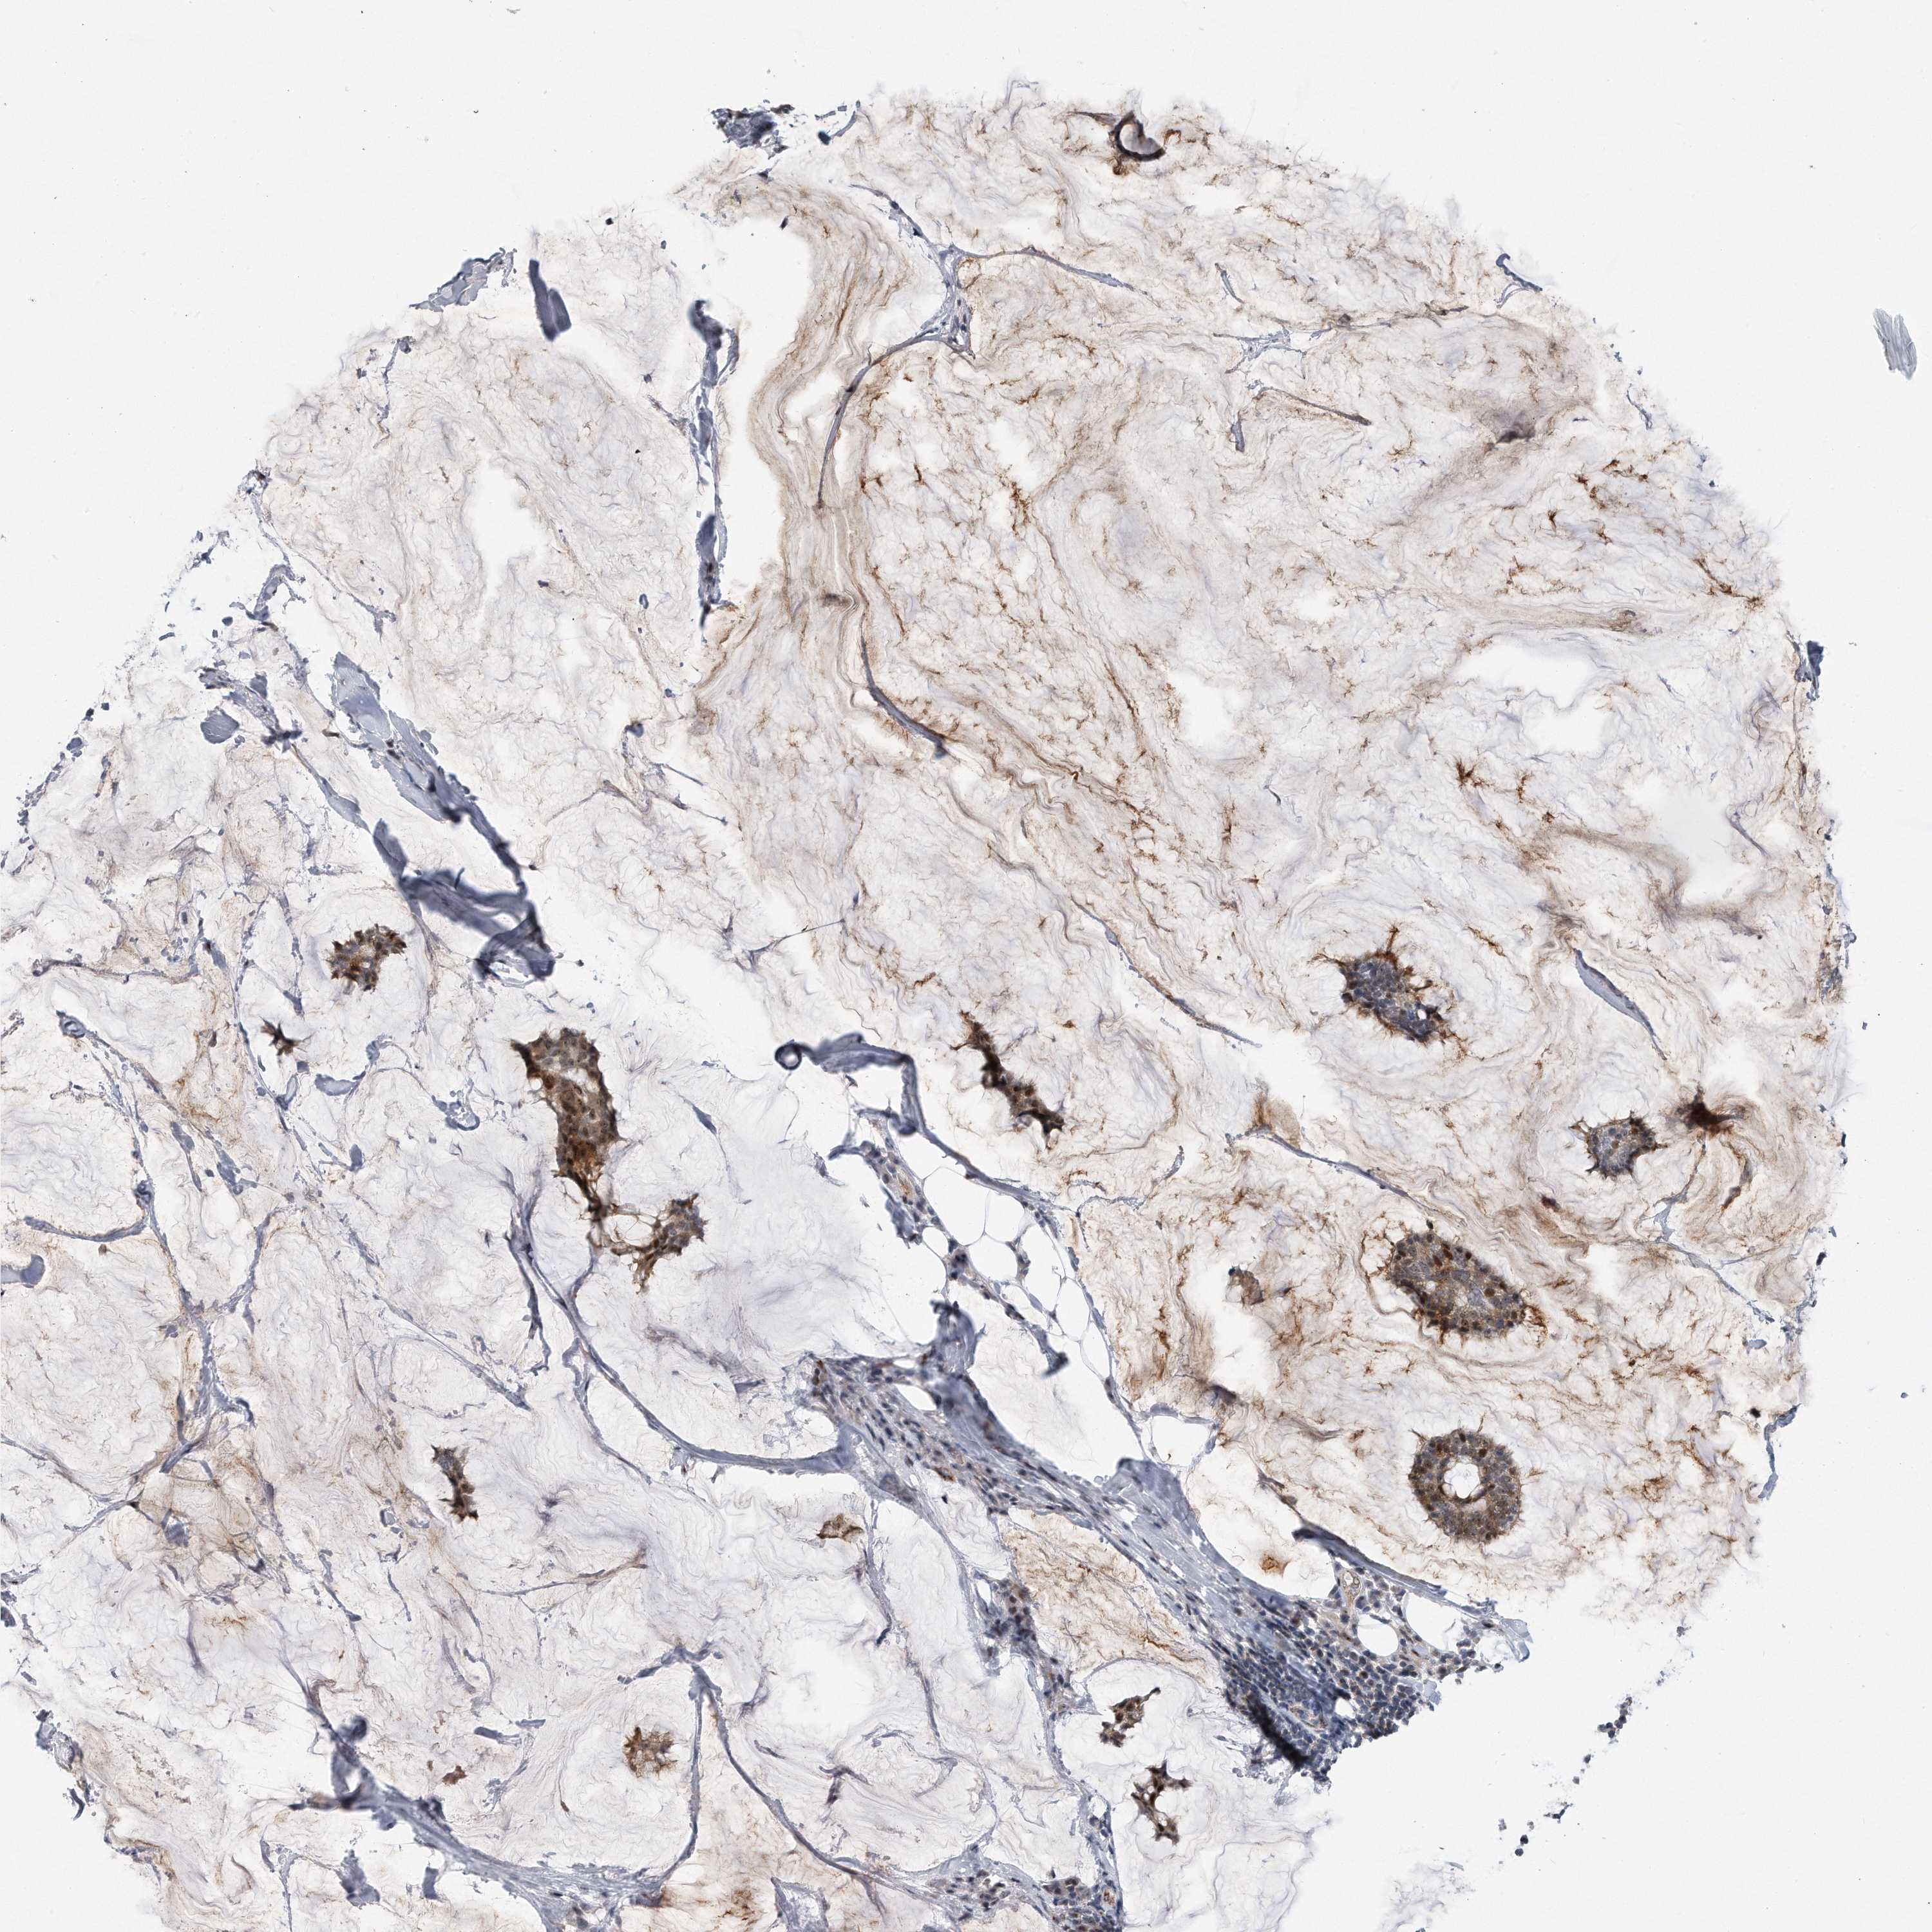

BRCA TCGA BRCA VALIDATION PROTEIN EXPRESSION

ANTIBODIES

AND

VALIDATION